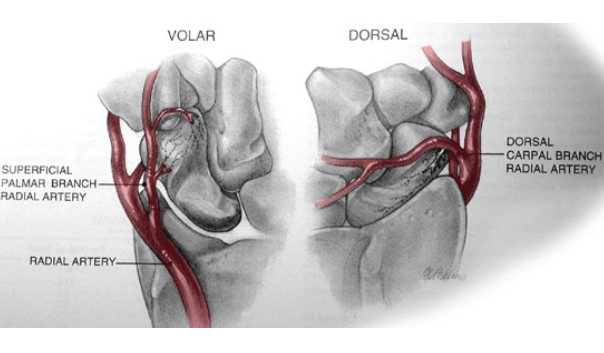

- Blood supply

- major supply- DORSAL CARPAL Branch of radial artery- enters scaphoid in a nonarticular ridge on dorsal surface and supplies proximal 80% scaphoid via a RETROGRADE blood flow

- minor via SUPERFICIAL PALMAR Arch branch of volar radial artery- enters DIstal TUBERCLE and supplies 20% DISTAL SCAPHOID